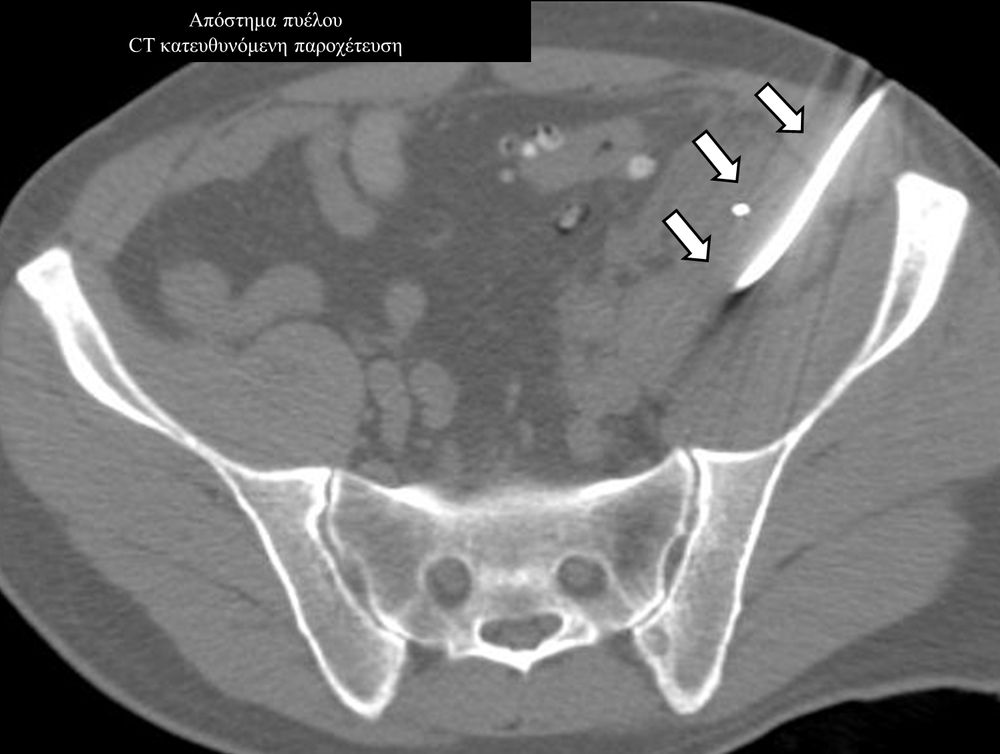

Η παρέμβαση διενεργείται υπό την καθοδήγηση αξονικού τομογράφου ή υπερήχων ή και με συνδυασμό τους. Ο επεμβατικός ακτινολόγος αρχικά αναισθητοποιεί την ανατομική περιοχή ενδιαφέροντος με τη χρήση τοπικής αναισθησίας και παρακεντεί την συλλογή διαδερμικά με λεπτή βελόνη. Στη συνέχεια μέσω ομοαξονικών συστημάτων συρμάτων-καθετήρων-διαστολέωντοποθετείται διαδερμικός καθετήρας τύπου pig-tail εντός της συλλογής, ο οποίος συνδέεται με εξωτερική παροχέτευση.